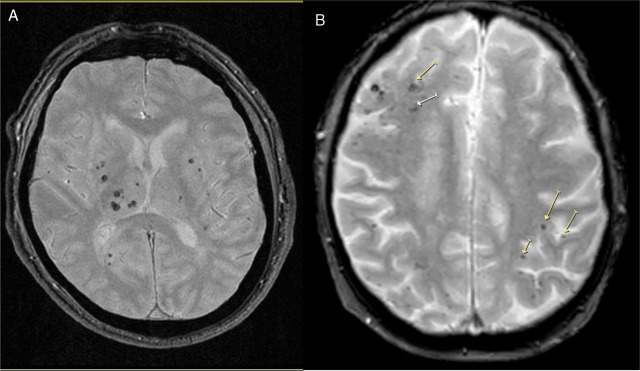

La presencia de enfermedad de vasos cerebrales pequeños en la resonancia magnética de adultos asintomáticos se asoció de manera independiente con un deterioro del funcionamiento ejecutivo durante un período de seguimiento de 8 años en esta población general coreana de edad mediana a avanzada. The Lancet Regional Health Western Pacific, febrero de 2025.